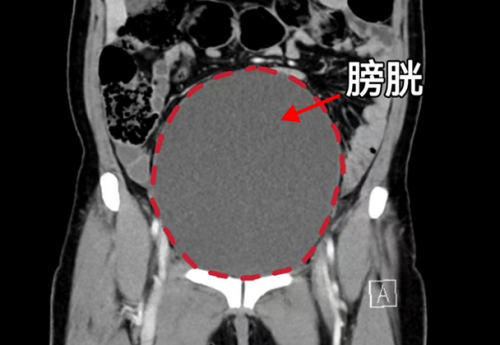

CT显示膀胱高度膨胀、尿道梗阻

“患者20余年前就因咳嗽后溢尿就医,诊断出子宫脱垂,因为担心手术风险一直没有接受治疗,半个月之前老人出现尿频、尿痛、排尿困难,忍着没和家里人说,直到6月4日,发现有肿块从阴道口脱出,内裤上有血迹才被家人送医。”据立博体育 妇产科三区主任魏馨介绍,经检查发现患者为子宫脱垂三度(Ⅳ期),子宫和阴道前后壁完全脱出阴道口,由于脱出的组织压迫尿道,造成尿道梗阻、尿潴留、泌尿系感染,同时还合并有支气管扩张并感染、低蛋白血症、轻度贫血等情况。